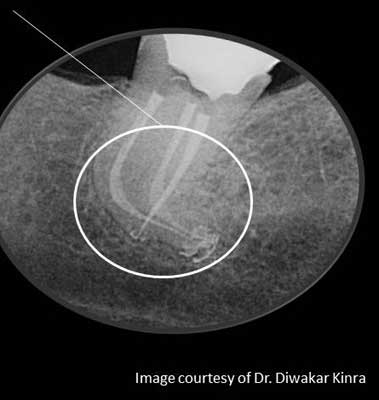

Characteristics of well-done obturation are defined and categorized as the three-dimensional filling of the entire root canal system as close to the cemento-dentinal junction as possible; i.e., without gross overextension or underfilling in the presence of a patent canal. Minimal amounts of root canal sealers — most of which have been shown to be biocompatible or tolerated by the tissues in their set state — are used in conjunction with the core filling material to establish an adequate seal. However, it is only through a knowledgeable approach to root canal treatment that quality assurance can be continually demonstrated in the obturation of the canal system. (7)